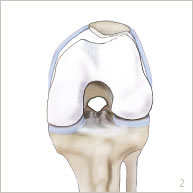

Le genou correspond à l’articulation entre le fémur, le tibia et la rotule. Les surfaces articulaires sont recouvertes de cartilage. La stabilité de la rotule est assurée par le tendon quadricipital en haut, le tendon rotulien en bas et les ailerons rotuliens sur les côtés. Les ailerons sont des sortes de rubans plus ou moins élastiques reliant la rotule au fémur (figures 1 et 5).

La rotule s’emboîte dans la trochlée du fémur qui est une gorge plus ou moins profonde. Cet emboîtement harmonieux dépend des formes osseuses, des tendons et des ailerons rotuliens.